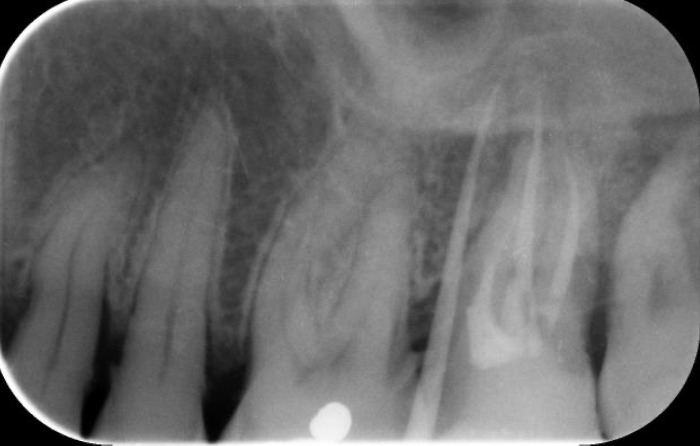

Présence d’un abcès dû à une racine complexe à désinfecter.

L’amputation radiculaire est un traitement de compromis qui peut parfois être proposé dans certains cas où une racine d’une dent à plusieurs racines est responsable d’une infection. Il s’agit de retirer la racine impossible à désinfecter et de garder les racines restantes permettant quand même de conserver la dent à terme. Ce type d’intervention est dans les compétences du Dr. Karim HSSINA et permet de conserver les dents.